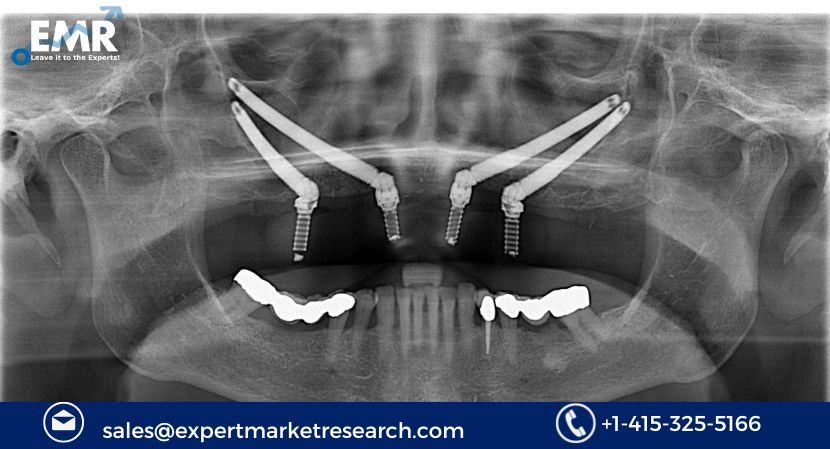

Zygomatic and pterygoid implants have emerged as innovative solutions in implant dentistry for patients with severe bone loss in the upper jaw. These advanced dental implant systems provide an alternative to traditional implant techniques that require sufficient bone for successful integration. Zygomatic implants are anchored in the zygomatic bone, while pterygoid implants are placed in the pterygoid region, offering stability and support for dental restorations.

The introduction of zygomatic and pterygoid implants has revolutionized the treatment options for patients with challenging anatomical conditions. These implants provide a reliable and durable foundation for the placement of prosthetic teeth, restoring aesthetics, function, and confidence to individuals with significant bone deficiencies in the upper jaw.